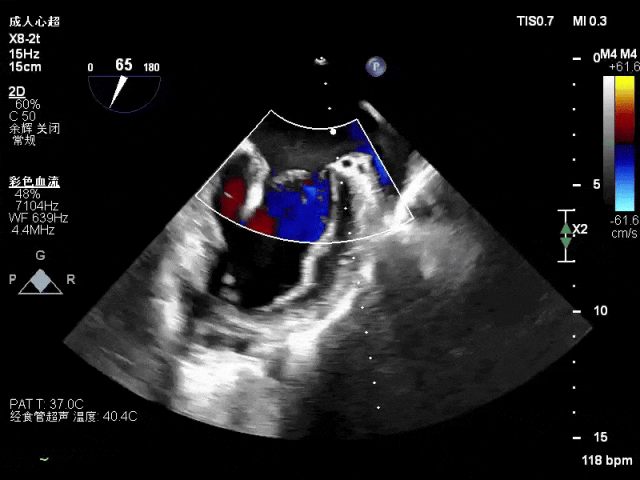

术前术后对比图:

术前

术后

术后,出院检查报告显示夹子位置固定,无移位,二尖瓣轻度反流,左室大小和LVEF值正常范围,左室壁运动分析未见明显异常。术后两个月随访检查,状态稳定,夹子位置固定,二尖瓣轻度反流,左室大小和LVEF值正常范围,左室壁运动分析未见明显异常(左室壁运动记分指数1分)。